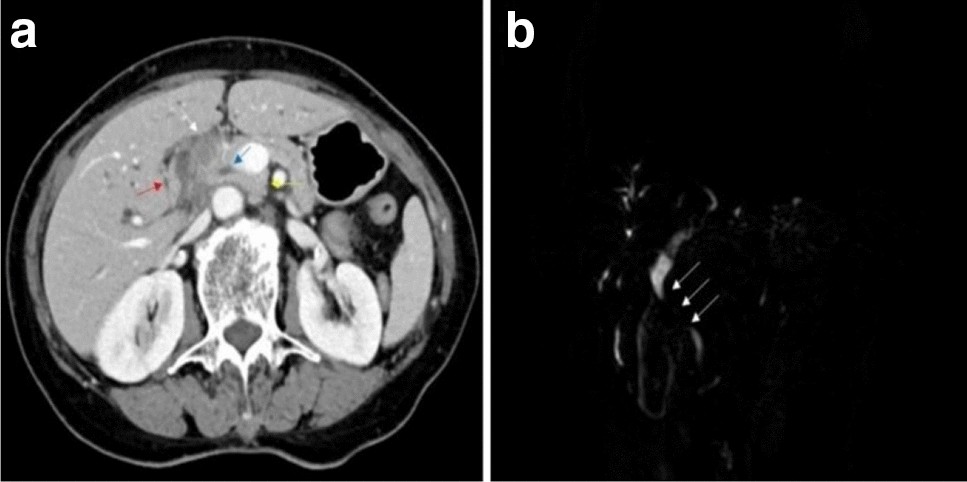

Computed tomography (a) and magnetic resonance imaging (b) showed stenosis at the common hepatic duct and the upper segment of the common bile duct (a The white arrow indicates the soft tissue shadow, the blue arrow indicates the common bile duct, the red arrow indicates the duodenum, and the yellow arrow indicates the head of the pancreas. b The white arrow indicates the stenosis.).